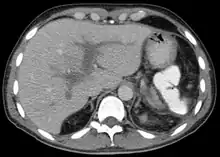

| Portal vein thrombosis seen with computed tomography. | |